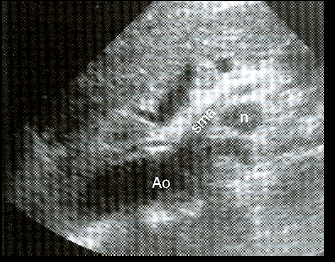

what are these examples of?

paraortic lymph nodes (pt has history of AIDS)